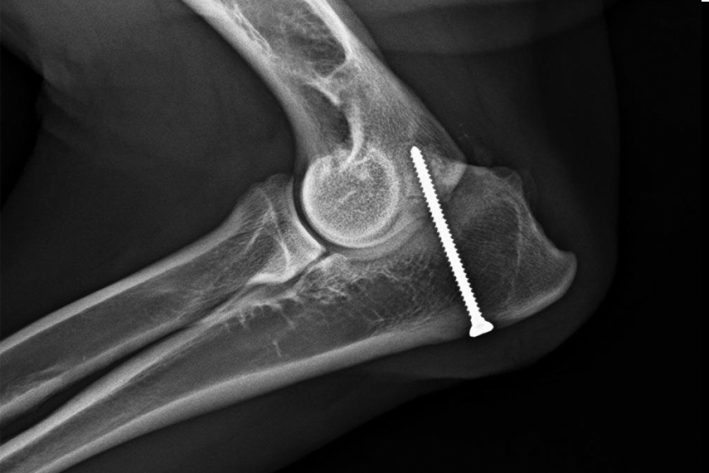

Sofern noch keine Arthrosen vorliegen, kann die Fusion (Vereinigung) des Proc. anconeus versucht werden. Bei sehr jungen Hunden mit Ellbogendysplasie, bei denen ein „short ulna“ Syndrom, also eine verkürzte Elle vorliegt, kann manchmal allein durch eine sogenannte „Ulnaosteotomie“ eine Verbindung des Proc. anconeus mit der Elle hergestellt werden. Die Ulnaosteotomie ermöglicht ein Rutschen der Elle in ihre normale Position und damit eine Verlängerung der Elle. Hunde, die etwas älter sind, werden durch Anschrauben des Proc. anconeus behandelt. Im Falle eines „short ulna“ Syndroms wird eine Kombination aus Anschrauben und Ulnaosteotomie durchgeführt. Manchmal werden die Hunde erst vorgestellt, wenn sie ausgewachsen sind, oder wenn bereits starke Arthrosen vorliegen. In diesen Fällen kann der Proc. anconeus nur noch chirurgisch entfernt werden. Das Gelenk wird dadurch nur minimal destabilisiert und die Hunde zeigen in der Regel keine Probleme nach einer Entfernung.

Isolierter Proc. Anconeus

Isolierter Pro. Anconeus vor dem Anschrauben

Proc. Anconeus Mit Schraube

Isolierter Proc. Anconeus nach dem Anschrauben